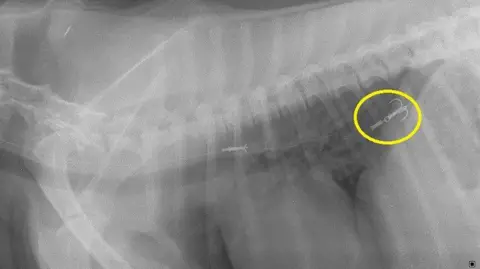

This week, Iran appointed a new supreme leader, a German city had to be evacuated when a large WW2 bomb was found, and the UK got a first listen to its unusual entry for this year's Eurovision song contest. But how much attention did you pay to what else happened in the world over the past seven days? Quiz collated by Ben Fell. Fancy some more? Try last week's quiz, or have a go at something from the archives. They treated three dogs for fish hook injuries in just one month - including a spaniel called Chip from Stranraer. Lynn Symphorien said Guernsey animals are now recognised for their quality in the UK. People Failsworth are continuing to search for the last of the dogs that were in the van at the time. Lurcher-collie cross Storm fell off the cliff ending up on a ledge 20m (66ft) below. Scientists have found further evidence that pet flea treatments are widespread in rivers across the UK.